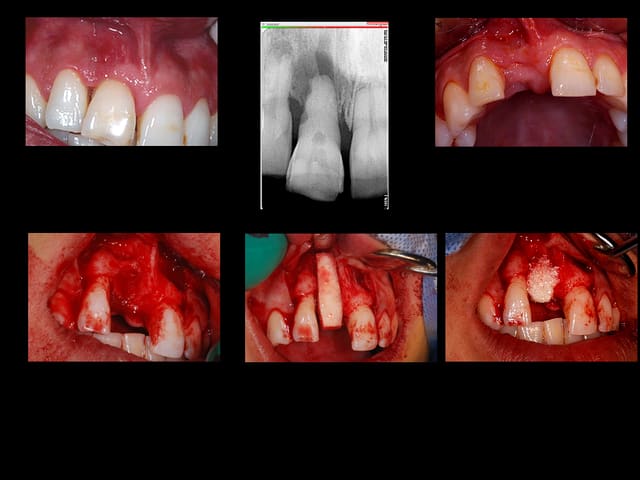

encore un ptit cas...sympa si on veut...car là j'ai besoin de l'expérience de ceux qui font çà souvent...

patient 17 ans...bientôt 18...

trauma dans l'enfance sur 11 et 21

pour la 21, çà va...mais la 11 est à bout de souffle...avec l'apex qui traverse la gencive vestibulaire...

veut un implant...forcément...mais là, faut une greffe...plutôt importante...

oui mac...mais une fois la 11 partie, je suis pas sûr que l'esthétique soit top...reste pas grand chose de la crête...une fois le travail de sape de la résorption osseuse faite....et il y aura de toutes façons une belle concavité vestibulaire...

Sinon concernant ton cas j'ai l'impression qu'il y a de l'os en mesial et distal de ta dent du coup si c'est bien le cas je ferais de la rog avec une membrane pinsee

Growler, ton cas avec greffe en bloc allogreffe as-tu une radio post-op? la hauteur cervicale du greffon avec la perte osseuse au mésial de la 12 m'inquiète?